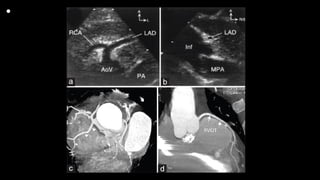

• This still frame image

of a parasternal short

axis view of the

echocardiogram of a

patient with tetralogy

of Fallot demonstrates

the antero-cephalad

deviation of the outlet

septum into the right

ventricular outflow

tract.

• A slightly modified view (a), angled to optimize

imaging of the pulmonary arteries in the patient

imaged to produce Figure 6, reveals significant

hypoplasia of the pulmonary trunk and the

pulmonary arteries, which result from the antero-

cephalad deviation of the outlet septum. The

pulmonary valvar leaflets are not visualized. In panel

b, colour Doppler has been used, and demonstrates

turbulence and acceleration of the flow of blood in

the right ventricular outflow tract, originating at the

level of the deviated outlet septum. The turbulence

continues into the hypoplastic pulmonary trunk and

pulmonary arteries.

• Figure 4: Origin of the LAD from the RCA crossing the right

ventricular outflow tract. (a) High parasternal short-axis view.

The enlarged proximal RCA supplies the LAD. (b) Leftward

angled parasternal long-axis view profiling the right ventricular

outflow tract (infundibulum) free wall. The LAD is seen in cross-

section approximately 7 mm below the pulmonary valve[25] and

52-year-old male, status post TOF repair. (c) Anomalous origin

of the LAD from the right coronary cusp (arrowhead). (d) The

anomalous LAD courses anterior to the RVOT (arrows).

(reproduced with permission from Kapur S, Aeron G, Vojta CN.

Pictorial review of coronary anomalies in Tetralogy of Fallot. J

Cardiovasc Comput Tomogr. 2015 Nov-Dec; 9(6):593-6.). A:

Anterior, AoV: Aortic valve, Inf: Infundibulum, L: Left, LAD: Left

anterior descending coronary artery, MPA: Main pulmonary

artery, RCA: Right coronary artery, R/S: Right/superior, RVOT:

Right ventricular outflow tract